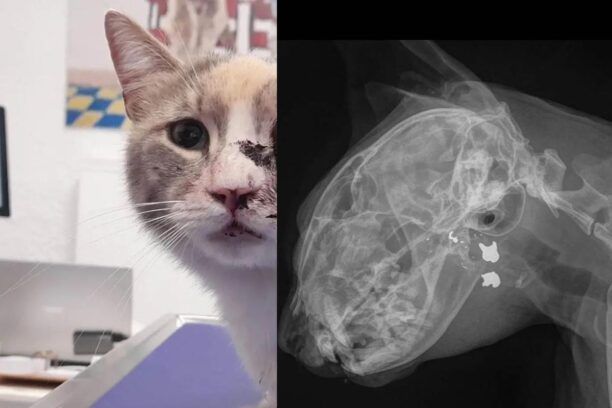

Στην αφαίρεση του ματιού μιας γάτας που στις 5 Μαρτίου εντοπίστηκε σε κατάσταση σοκ στις Σπέτσες στην περιοχή Κοκκιναριά προχώρησαν οι κτηνίατροι καθώς όπως διαπιστώθηκε το ζώο είχε πυροβοληθεί στο κεφάλι με αποτέλεσμα να διαλυθεί το αριστερό του μάτι.

Η Α.Μ.Κ.Ε. «Spetses Care For Animals» στην ανακοίνωση της για τον βασανισμό του ζώου επισήμανε τα εξής: «Το βράδυ της περασμένης Κυριακής μας κάλεσαν εκτάκτως για μια τραυματισμενη γάτα στο μάτι. Δεχτήκαμε άμεσα το περιστατικό, δώσαμε τις πρώτες βοήθειες και σταθεροποιήσαμε το ζώο που βρισκόταν σε σοκ.

Κατά τη διερεύνηση του περιστατικού βγάλαμε ακτινογραφίες και λυπημένοι και σοκαρισμένοι διαπιστώσαμε ότι το ζώο είχε τραυματιστεί με σκάγια αεροβόλου όπλου και μάλιστα δεν ήταν πρώτη φορά αφού βρέθηκε και ένα σκάγι στην κοιλιακή χώρα από παρελθόντα χρόνο.

Αφού έγιναν οι απαραίτητες αιματολογικές εξετάσεις προχωρήσαμε σε εξόρυξη του διαλυμένου οφθαλμού και παράλληλα σε στείρωση της γατούλας.

1η φωτογραφία το μάτι γάτας στο χειρουργείο

2η φωτογραφία ή γάτα στην κλινική μας

3η φωτογραφία ακτινογραφία το κεφάλι της γάτας που φαίνεται το σκάγι